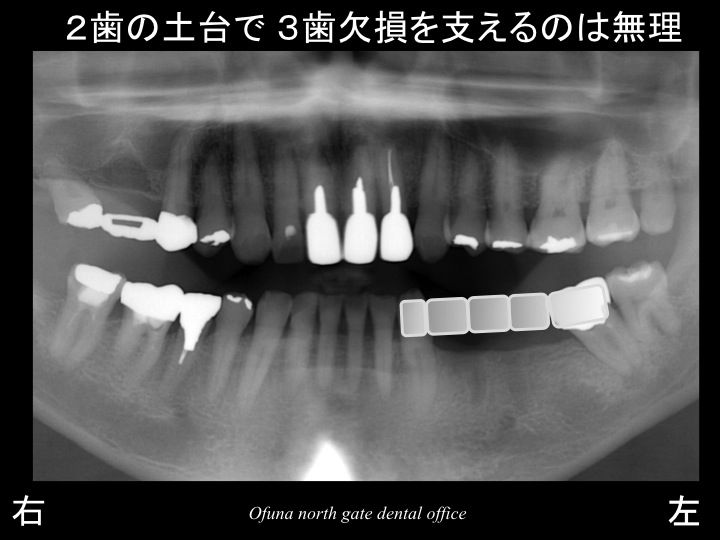

早速初診時のレントゲンを見てみましょう!

下顎左側の奥歯が3歯分欠損していました。

また 今回のケースの場合、

欠損部が3歯分ありますので、その両側の歯を削っただけでは、

維持力としてはかなり不安が残ります。

また、維持力を増すために、土台となる歯を増やすことも考えられますが、

奥歯の3歯欠損を支えるためには、必要となる土台は、それ以上の歯数が必要です。

つまり、ブリッジを行なうためには、4歯分の歯を土台とした方が安定が良いのです。